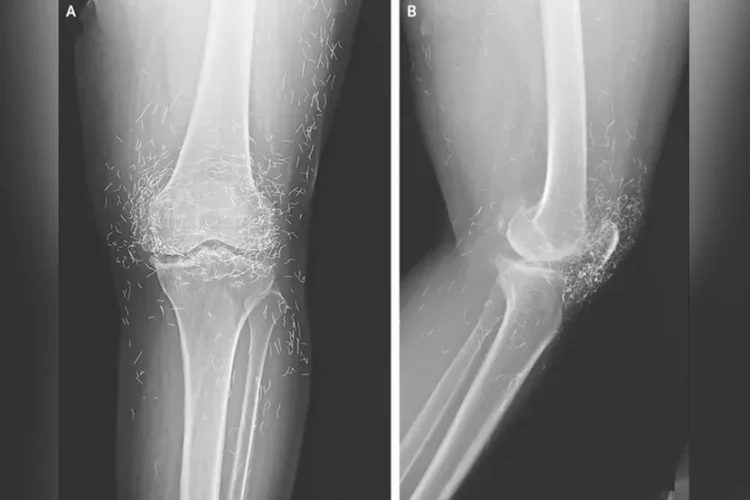

Photo: The New England Journal of Medicine

An X-ray exam revealed a thickening and hardening of the inner part of the tibia, bony growths in the knee, all common symptoms of osteoarthritis – but also hundreds of tiny gold threads embedded in the tissue around the knee. Doctors warn that gold thread acupuncture has no scientifically-proven benefit for the patient, but comes with many known risks. The tiny threads can cause cysts, migrate into the body, and damage surrounding tissue, but they can also make potentially life-saving MRI scans impossible because of the risk of metal displacement and blood vessel damage.